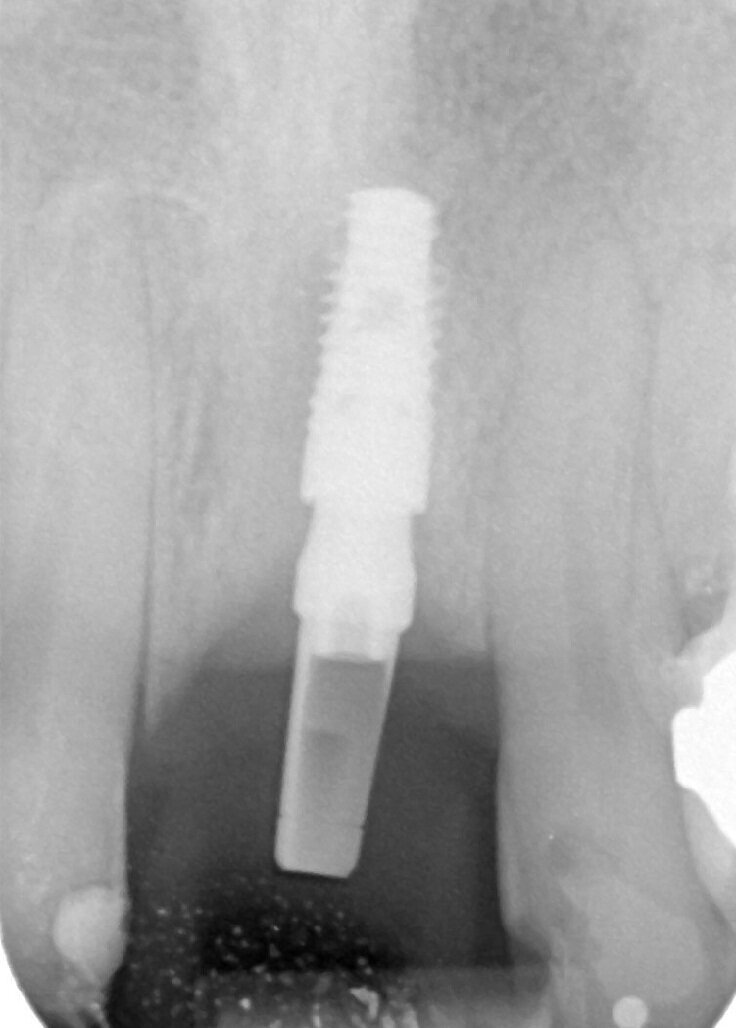

Paziente di sesso maschile di 60 anni di età giunto alla nostra osservazione per una edentulia parziale dovuta all’assenza dell’elemento 1,1. La situazione clinica è resa esteticamente e funzionalmente complicata dalla assenza dell’elemento 2,2 che considerato lo spostamento dei denti contigui comporta un aumentato spazio per la sostituzione protesica dell’elemento 1.1. Si effettua dopo rx di controllo il posizionamento di un impianto osteintegrato GTB diametro 3,6 x 9 mm ,con posizionamento, come da protocollo, 1,5 mm sottocrestale ed inserzione immediata di moncone easy abutment slim 3,4 x 7 mm altezza gengivale 3,5 mm. angolato a 10 gradi (Easy Abutment Slim – GTB Plan1Health Amaro, UD, Italy). Con l’ausilio di una cappetta easy si costruisce e si cementa, con tecnica extraorale, una corona provvisoria in resina acrilica con forma a pontic su elemento 1.1 in modo da eseguire un carico immediato e fornire al paziente una estetica immediata (Figg. 1-3). Dopo 12 settimane ad avvenuta osteointegrazione si provvede all’impronta definitiva eseguita a livello abutment con elastomero di precisione Aquasyl Monophase (Dentsply) e con idonea cappetta easy (GTB Plan1Health Amaro, UD, Italy). La stessa cappetta easy viene utilizzata dal laboratorio odontotecnico come cappetta da sovrafusione garantendo standard di precisione stabiliti industrialmente (Figg. 4-8). La corona costruita in lega preziosa e porcellana viene cementata dopo una settimana, fatte le prove estetiche e occlusali necessarie sul paziente. I controlli a distanza di 4 anni, sia radiografici che clinici, confermano la stabilità dell’osso intorno all’impianto e la mancanza di perdita di tessuto gengivale attorno allo stesso (Figg. 9-11).

Fig. 2_Rx immediatamente dopo il posizionamento dell’impianto GTB e del Moncone Easy Slim. Notare la perfetta congruenza tra l’impianto e lo spazio di preparazione.